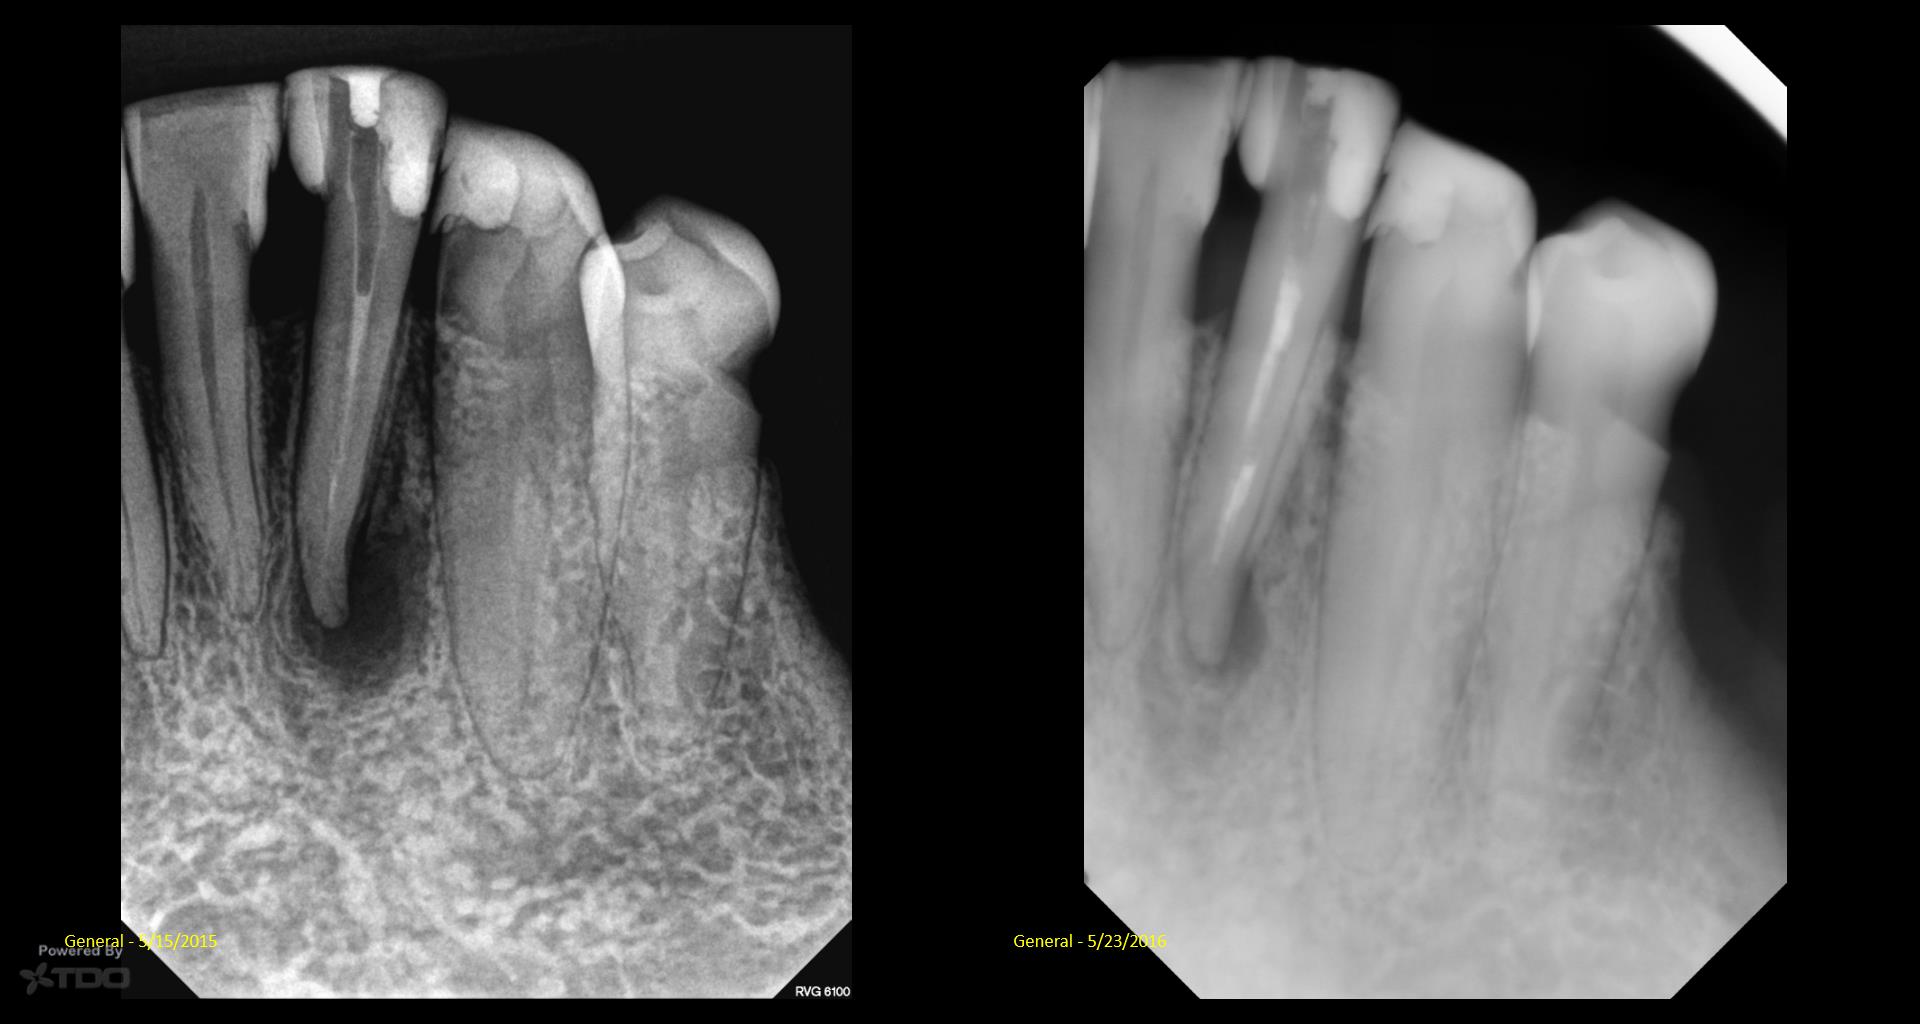

It’s a little embarrassing…but I have been treating a tooth of Joy’s for 5 years….Multiple CaOH visits over those 5 years. Coulod never get the area to resolve. Finally tried a GW on it…..1 yr recall today. gbc